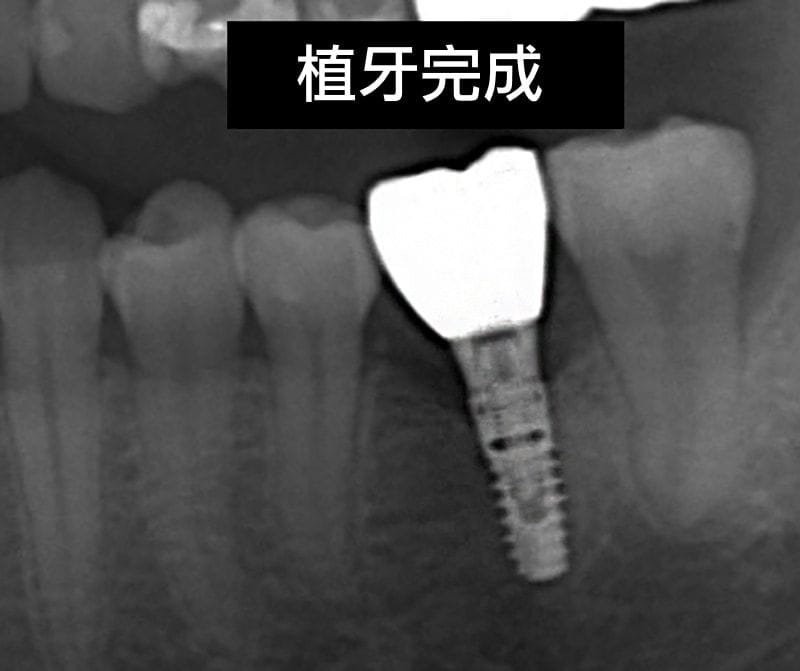

我們等待上顎半年、下顎三個月人工植牙骨整合的時間後,順利地把正式假牙完成。

圖示:植牙完成後裝上正式假牙的X光片 圖示:鼻竇增高術、補骨與植牙手術後,人工植體周圍骨頭狀況穩定